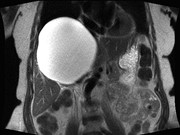

Cylindroma-like basaloid anal cancer presenting as a large pelvic mass in a patient with ulcerative colitis

Sugong Chen and others

Journal of Surgical Case Reports, Volume 2015, Issue 7, July 2015, rjv093, https://doi.org/10.1093/jscr/rjv093